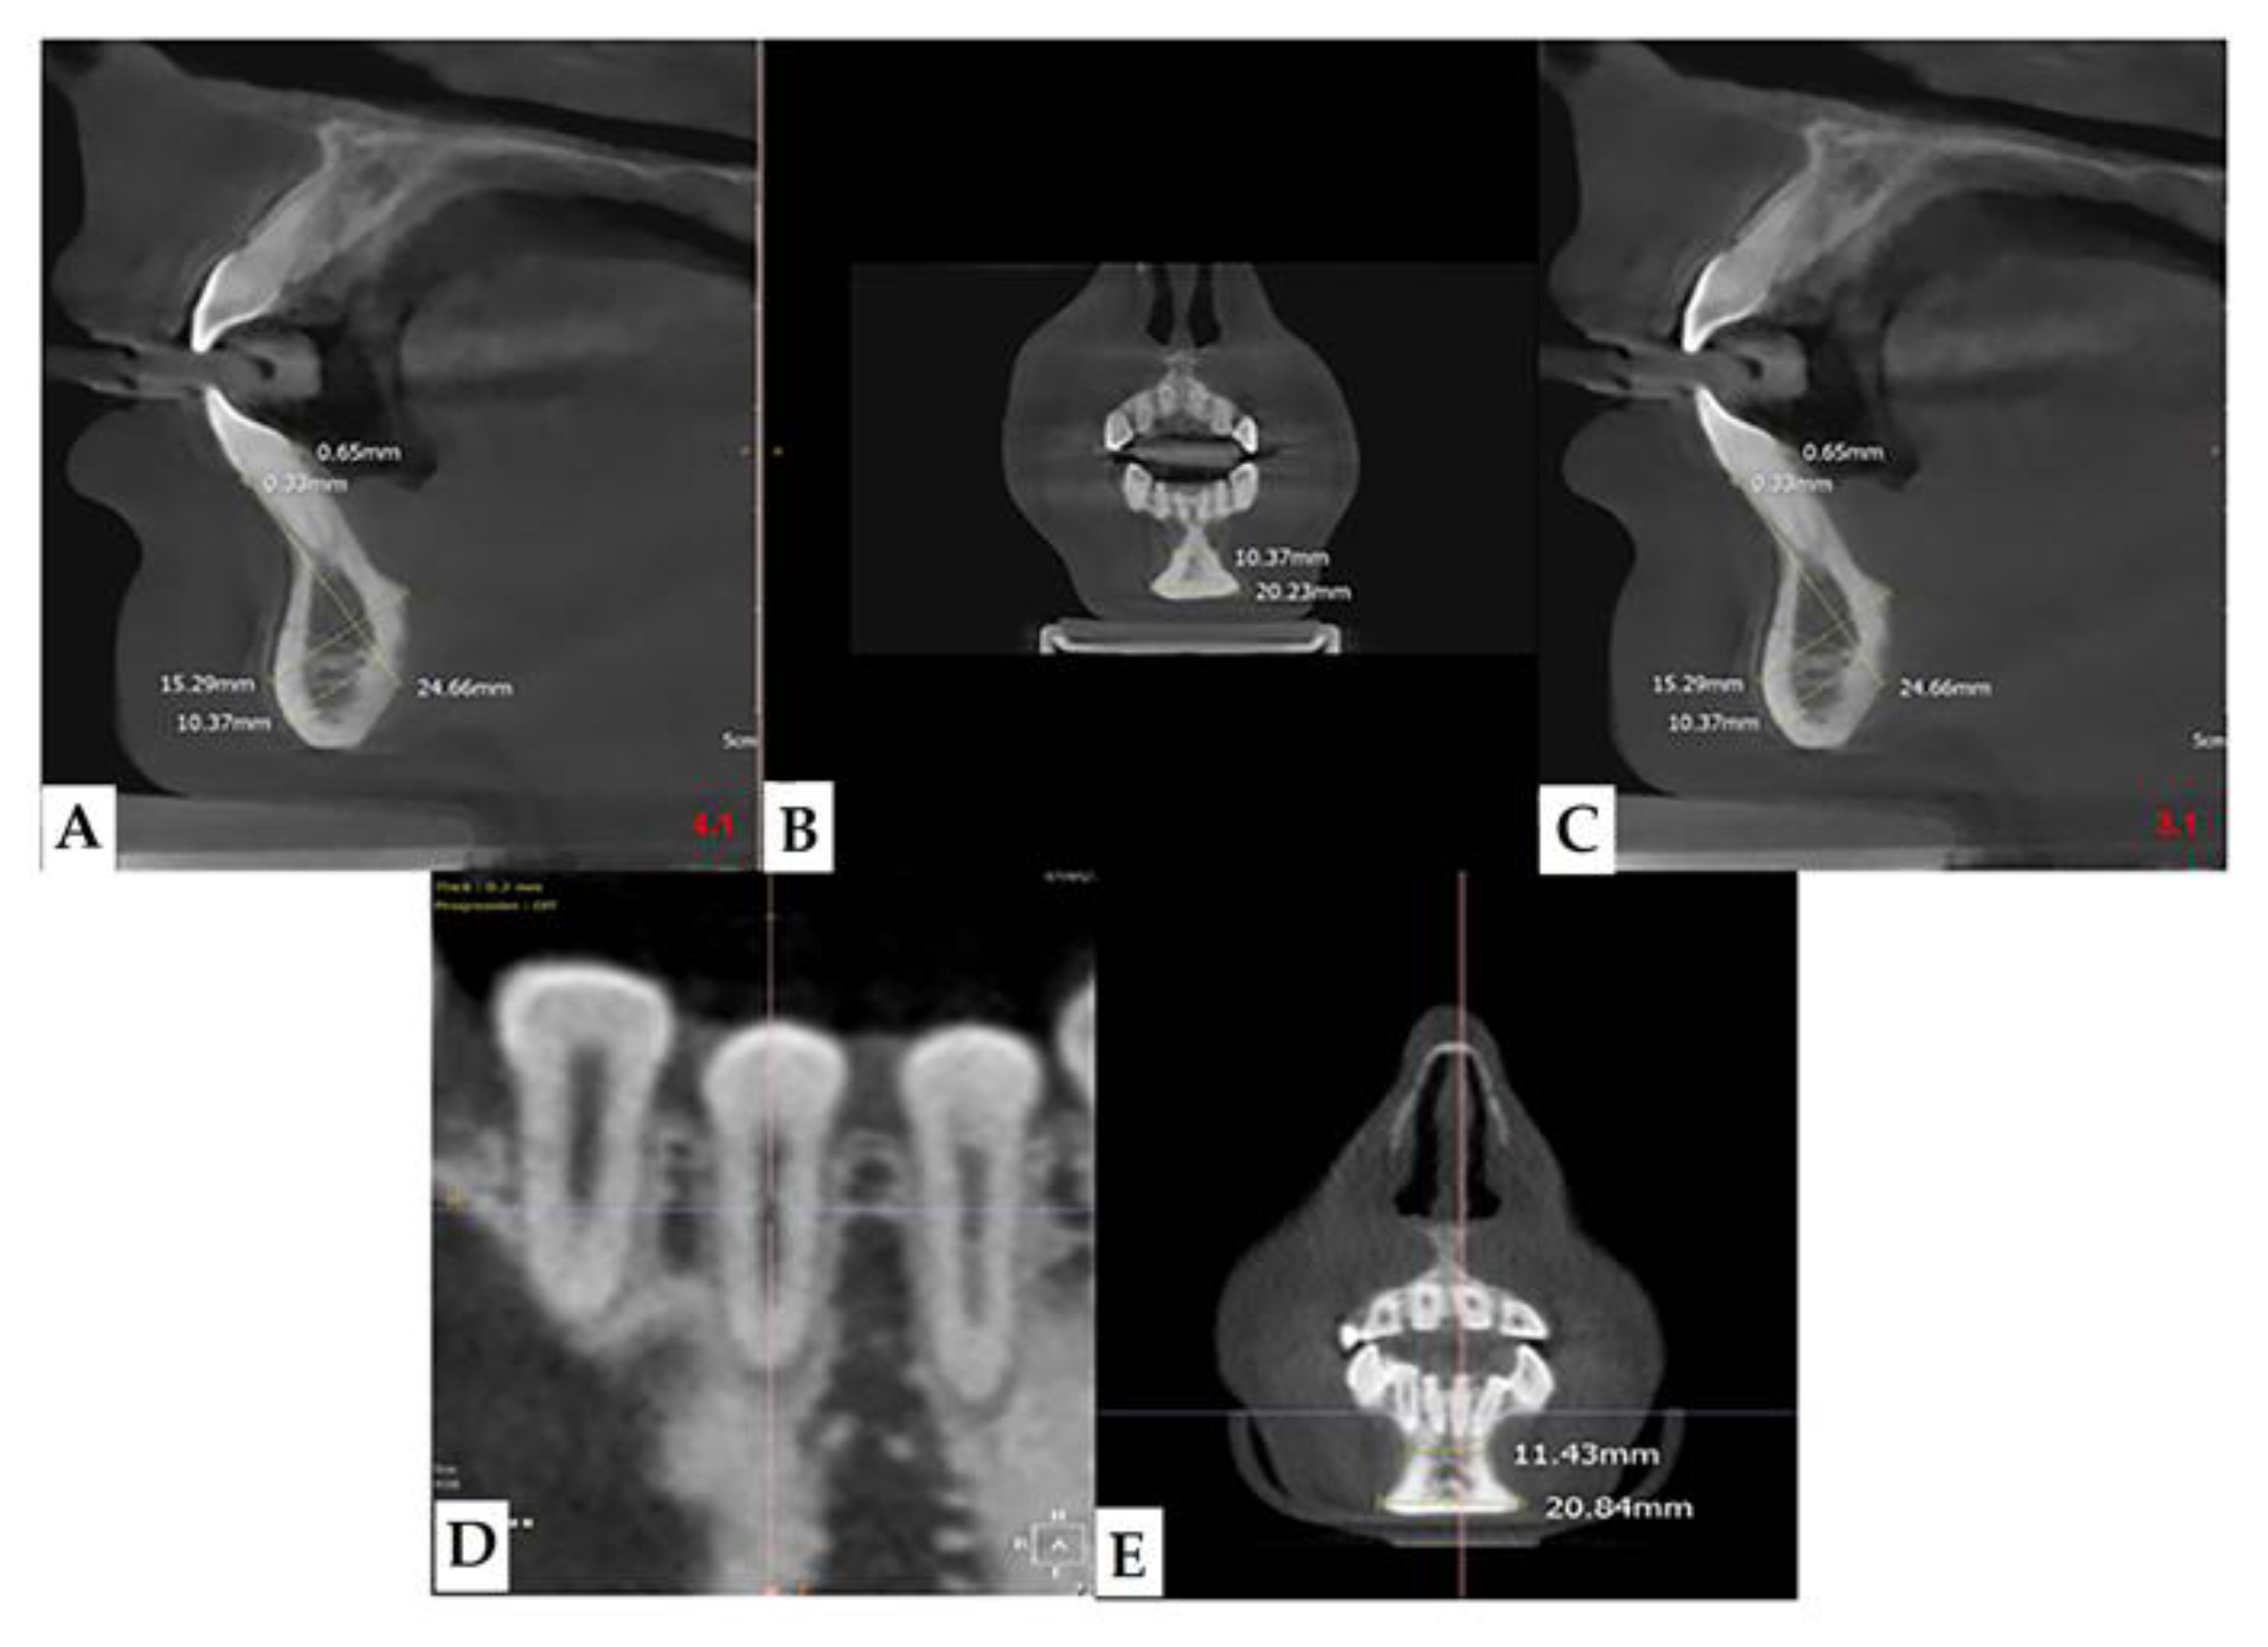

Many are the anatomical districts involved in OI, and many are the signs and symptoms, including bone fragility. The patient is treated clinically and predominantly for the complex picture that may arise related to the osteoporotic condition. The dental part is often treated in second-order and is generally limited to the treatment of DI. The observation of the characteristic facies of the patient means that, today, with the new methodologies, it is possible to deepen the single components of the anatomical alterations of the maxillofacial district which can be indicators of the severity of the disease. The dentoalveolar and craniofacial anomalies, detectable by imaging, are present in all types of OI, from mild to moderate to severe (Figure 7 and Figure 8). The facial appearance of patients with both moderate and severe OI is often characterized by the triangular shape of the skull, sometimes macrocephaly, the protrusion of both temporal bones, and the prominence of the frontal bone. In addition, they have a dolic-type facial biotype, with increased vertical diameters.

Figure 7. CBCT images showing bone resorption in the mandible anterior region in a patient with mild OI (A), sagittal 4.1, (B) coronal, (C) sagittal 3.1, (D), and (E) particular.

Figure 8. (A,B): Vestibular and lingual cortical reduction in zones 3.1 and 4.1 in patients with OI in the moderate-severe form. In the lower line of the Images (B) in the middle, there is a three-dimensional CBCT reconstruction that shows the very evident chin typical of OI.